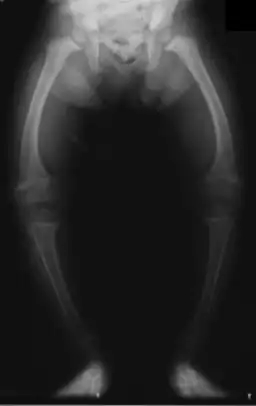

راشیتیسم یا نرمی استخوان یابیماری ریکتز نرم استی ( انگلیسی: Rickets ) یک بیماری مربوط به رشد استخوان ها است که در نوزادان و کودکان دیده می شود. در این بیماری استخوانهای کودکان به دلایلی نرم باقی می مانند. این بیماری موجب خمیدگی و رشد ناقص استخوان ها و افزایش ریسک شکستن آن ها می شود. علت اصلی بیماری راشیتیسم کمبود ویتامین د است، ولی کمبود کلسیم نیز در آن نقش دارد که موجب ترشح بیشتر هرمون پارا ترمون میگردد.

خمیدگی استخوان ها از علایم «کلاسیک» راشیتیسم است که در استخوان پاها و قفسهٔ سینه به وجود می آید. این نقص در جمجمه نیز ممکن است به وجود آید؛ در این صورت جمجمه حالت بیضی شکل خود را از دست می دهد. در صورت وخیم بودن بیماری، خمیدگی در استخوان های بلند و ستون مهره ها نیز ظاهر می شود. این خمیدگی ها با درمان در سنین کوکی معالجه می شوند.